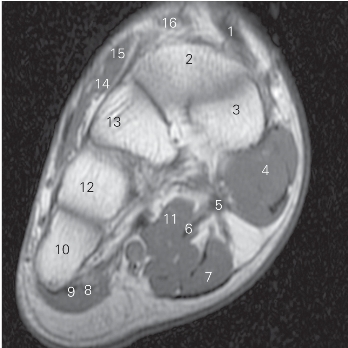

图5-50 经楔骨近段的横断层MR T1加权图像

1

长伸肌腱tendon of extensor hallucis longus

2 中间楔骨 intermediate cuneiform bone

3 内侧楔骨 medial cuneiform bone 4

展肌 abductor hallucis

5

长屈肌 flexor hallucis longus 6 趾长屈肌 flexor digitorum longus

7 趾短屈肌 flexor digitorum brevis

8 小趾短屈肌 flexor digiti minimi brevis

9 小趾展肌 abductor digiti minimi 10 第五跖骨 5th metatarsal bone

11 足底方肌 quadratus plantae 12 第四跖骨 4th metatarsal bone

13 外侧楔骨 lateral cuneiform bone

14 趾短伸肌腱 tendon of extensor digitorum brevis

15

短伸肌 extensor hallucis brevis

16 趾长伸肌 extensor digitorum longus

图5-51 经楔骨远段的横断层MR T1加权图像

2 胫骨前肌腱tendon of tibialis anterior 3 内侧楔骨 medial cuneiform bone

4

收肌 adductor hallucis 5

短屈肌 flexor hallucis brevis

6

长屈肌 flexor hallucis longus 7 趾长屈肌 flexor digitorum longus

8 趾短屈肌 flexor digitorum brevis 9 足底腱膜 plantar fascia

10 小趾短屈肌 flexor digiti minimi brevis

11 小趾展肌 abductor digiti minimi 12 第五跖骨 5th metatarsal bone

13 腓骨长肌腱 peroneus longus tendon

14 趾短伸肌 extensor digitorum brevis

15 外侧楔骨 lateral cuneiform bone

16 中间楔骨 intermediate cuneiform bone

17 趾长伸肌 extensor digitorum longus